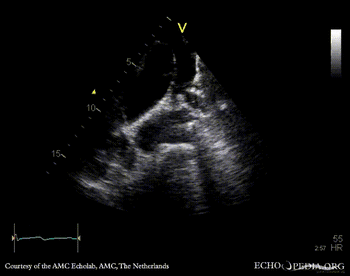

| Courtesy of: AMC Echolab, AMC, The Netherlands | |

| Suprasternal view | Suprasternal view with Color Doppler |